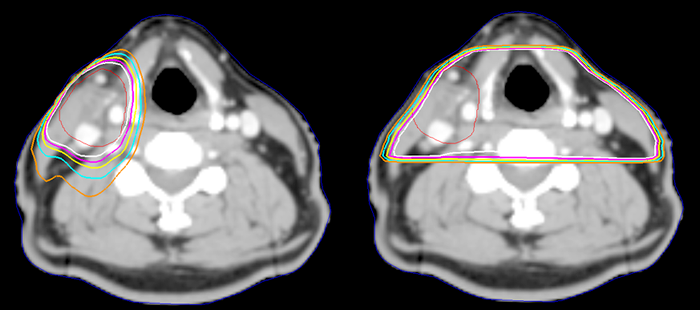

Above you can see two identical tumor volumes. The one on the Right has been planned with traditional lateral fields. The one on the Left has been treated with multi-field IMRT. Notice how much normal treatment is spared.